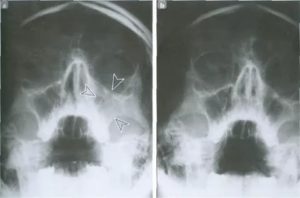

Одним из главных диагностических методов является рентгенография. В некоторых случаях может быть назначена компьютерная томография или МРТ. Выявление затемнения в левом верхнечелюстном синусе позволяет с высокой степенью уверенности диагностировать левосторонний гайморит.

На рентгене видны воспаленные очаги в гайморовых пазухах, симптомы которых – зеленые сопли и болевые ощущения. Также может назначаться и МРТ, чтобы проверить, есть ли воспалительные патологии, опухолевые процессы, полипы или лишняя жидкость в синусах. Она выявляет и искривления носовых каналов, а также распространение бактериального воспаления на другие соседние области.

Компьютерная томография раскрывает подробную карту костной и мягкотканой структуры верхнечелюстных пазух, отражая тип и характер разрушений в полостях и зоне носового скелета.

Такой способ диагностики необходим при травматическом гайморите, лечить который необходимо отличным от стандартного способом.

КТ указывает на присутствие инородных тел, объемных образованиях, орбитальных и внутричерепных осложнениях при хроническом синусите.